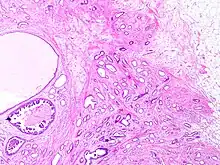

Tubular carcinomas are generally around 1 cm. or smaller, and are made up of tubules. They are usually low-grade.[2] Elastosis has been noted as common but is not present in all cases.[11]

- 1 2 Image by Mikael Häggström, MD. Reference for typical features: Pragya Virendrakumar Jain, M.D., Julie M. Jorns, M.D. "Breast - Other invasive carcinoma subtypes, WHO classified - Tubular". Pathology Outlines.

A highly differentiated invasive carcinoma that forms well-defined tubules (containing epithelium, but no myoepithelium) and that have abundant desmoplastic fibrous stromal reaction between the tubules.